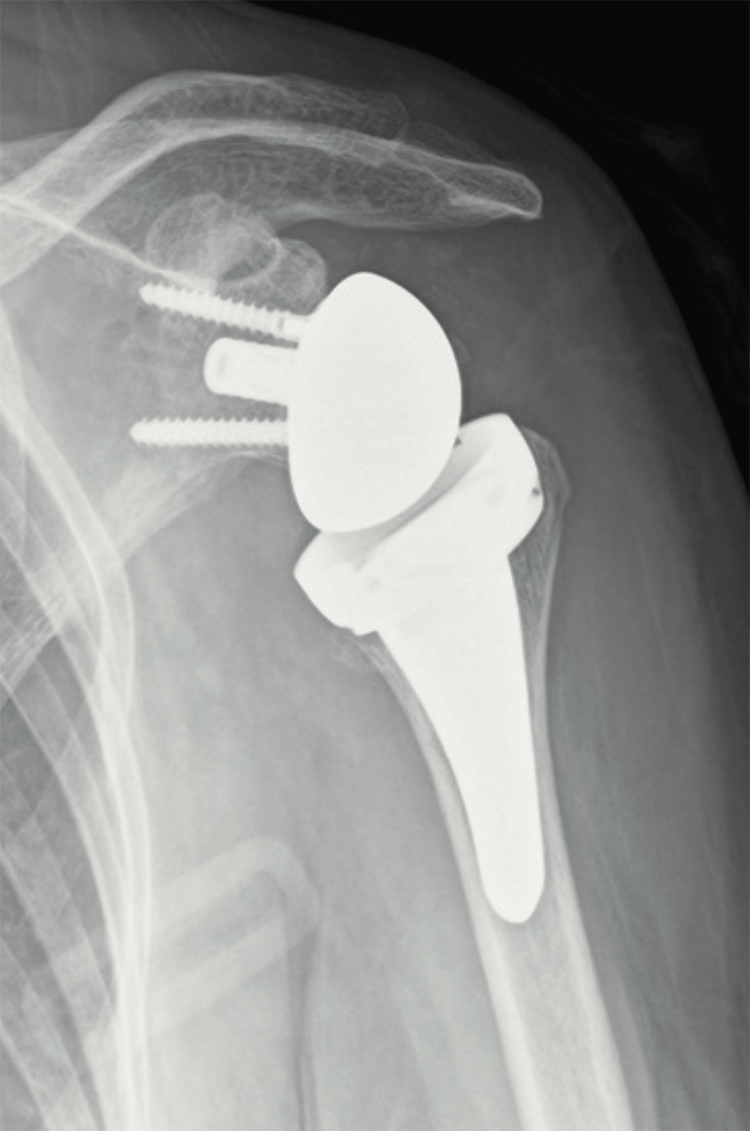

- 広範囲の大きな断裂で筋肉の萎縮が強い場合などは、腱板を付着部に修復することが困難な場合があります。修復不能が予想される場合は、リバース型人工肩関節置換術を行います。これは、関節窩(かんせつか)(本来の受け皿)に丸いボールを設置し、丸い上腕骨頭は切除して受け皿を設置するため、術後は通常の肩関節とは真逆の構造となります。本来、上腕骨が腱板筋の収縮で安定しないと、肩関節の挙上ができませんが、この関節は、その構造により三角筋の収縮で上腕骨が安定するため、腱板修復をしなくても肩関節挙上が可能になります(図5)。